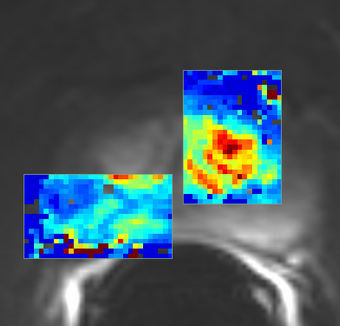

- ROI Mask Image (ROIMaskFileName): (Optional) Mask designating the voxels (non-zero) where the model should be fit. If not specified, the model will be fit to all voxels in the image.

- AIF Mask Image (AIFMaskFileName): Mask designating the location of the arterial input function (AIF). AIF can be calculated from a generic population AIF, the input using the aifMask or can be prescribed directly in concentration units using the prescribedAIF option.

- Output Ktrans image (OutputKtransFileName): Output volume transfer constant between blood plasma and EES (extracellular-extravascular space) at each voxel.

- Output ve image (OutputVeFileName): Output fractional volume for extracellular space at each voxel.

- Output AUC image (OutputAUCFileName): Output area under the curve (AUC) of each voxel, measured from bolus arrival time to the end time of interval, normalized by the AUC of the AIF.